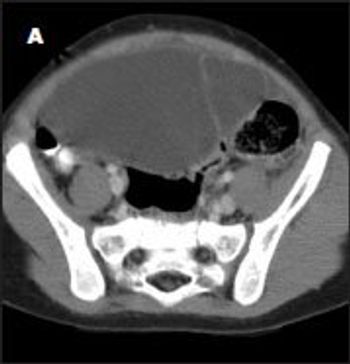

A 2-year-old girl was transferred to the pediatric ICU from a nearby community hospital because of nonremitting, generalized abdominal pain associated with fever and vomiting. Her symptoms had begun 3 days earlier and had progressively worsened despite treatment with antibiotics, pain medication, and fluids.